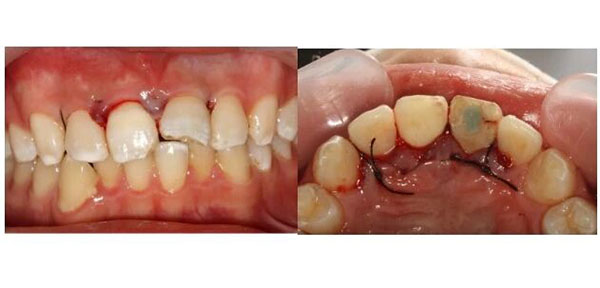

术后1周拆线,伤口长得不错。

术后2周,完成冠部的充填修复。

先完成根管治疗,把牙齿内部清理干净。然后,在手术显微镜下,翻开牙龈,暴露出深藏在牙槽骨里的断端,用纤维桩像“钢筋”一样打进牙根里,再把断下来的牙冠原样粘回去。